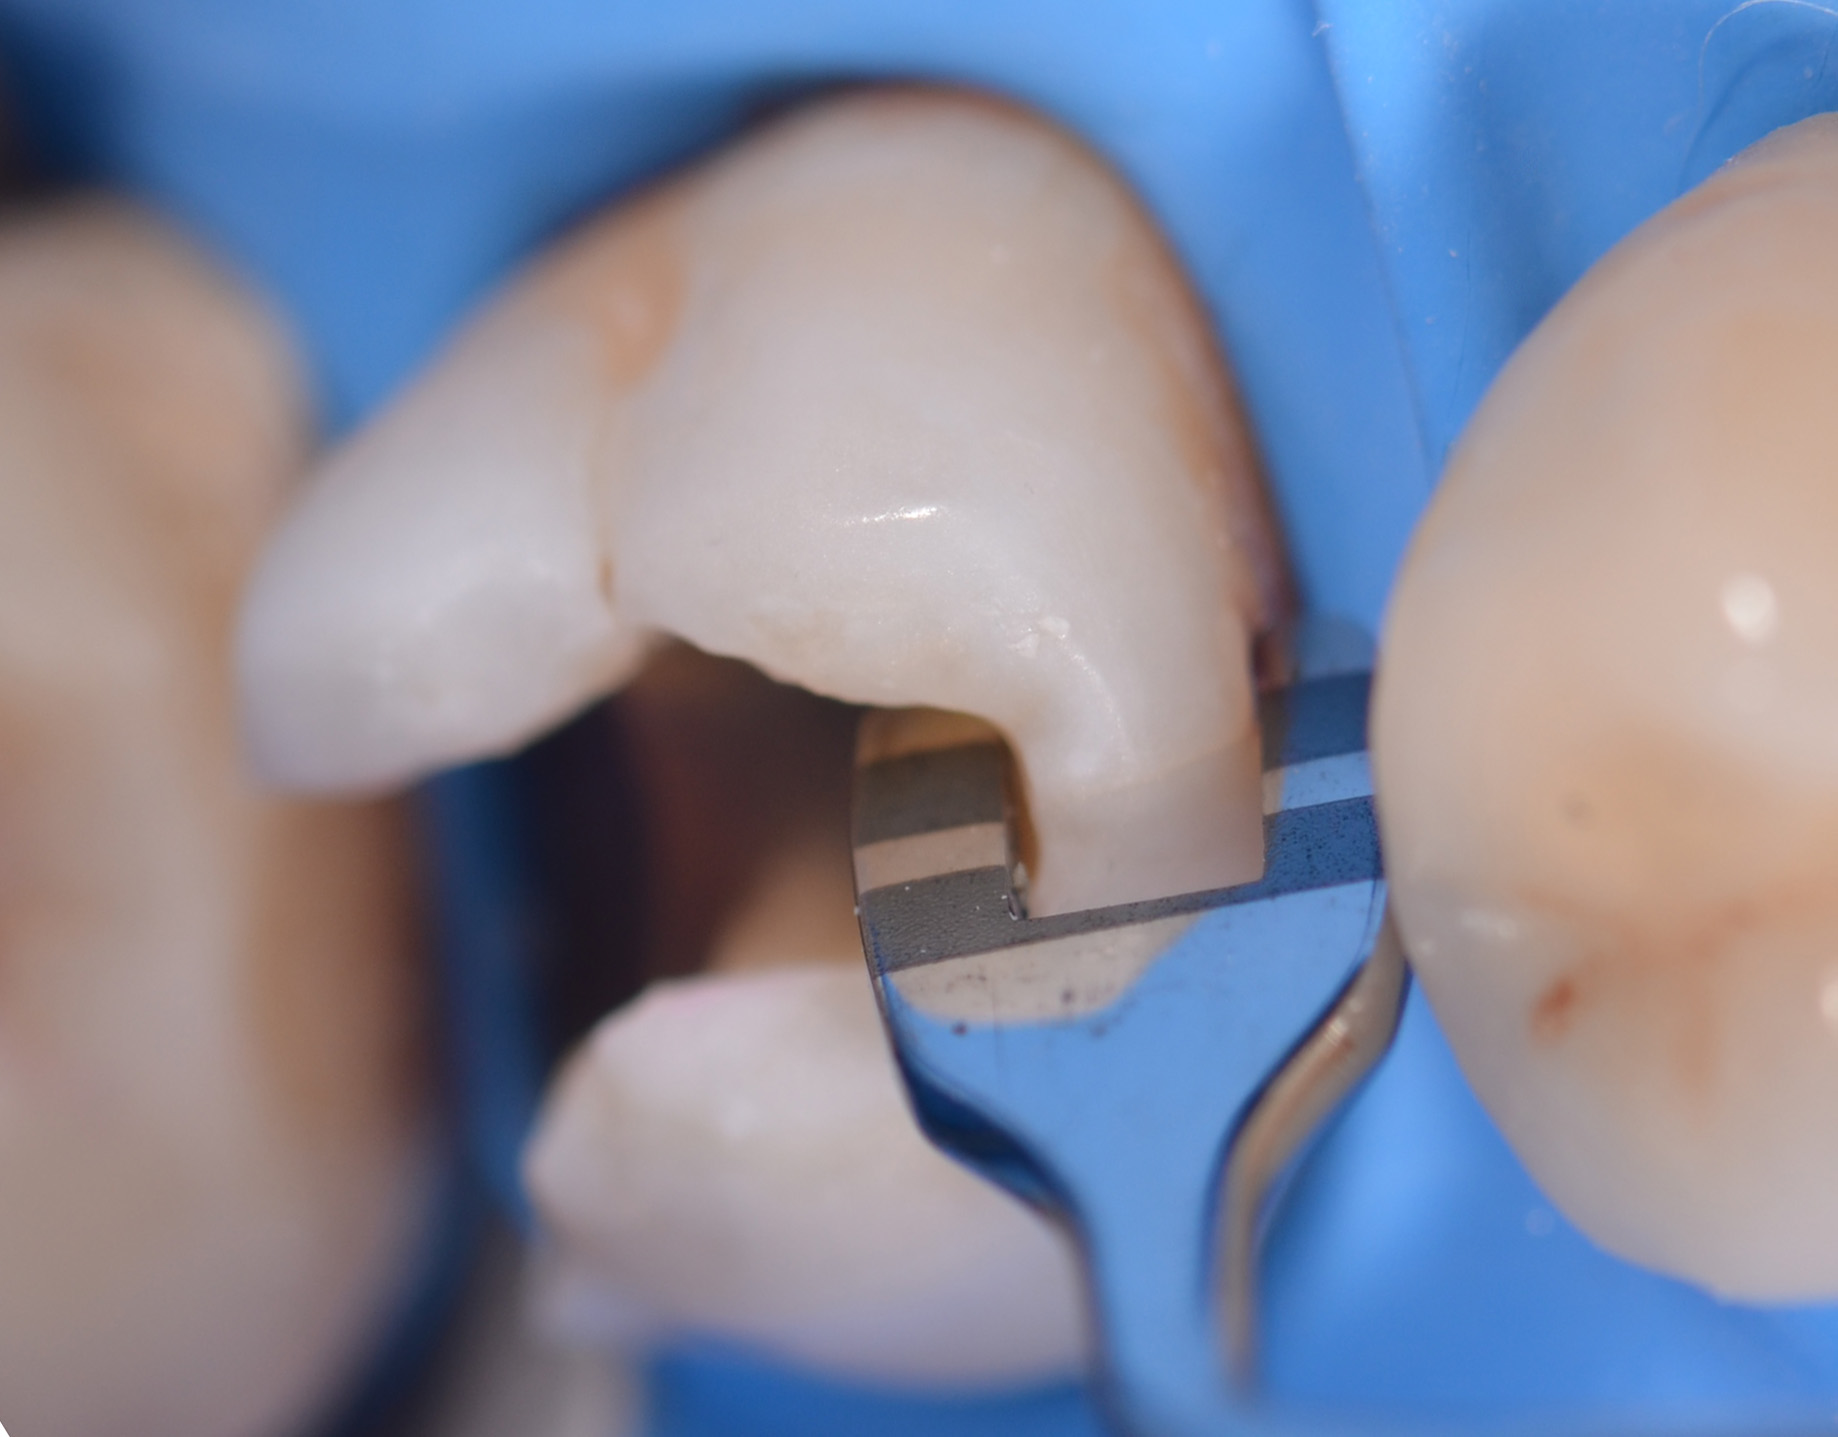

Si esegue anestesia plessica con rinforzo intraligamentoso mediante articaina 1:100.000 sull’elemento 1.6. Successivamente si isola il campo con diga in gomma, utilizzando una clamp 27N sull’elemento 1.7 (Figura 3) con invaginazione del foglio a livello dei colletti.

Una volta completata la rimozione della carie, si inserisce un cuneo interdentale (Composi-Tight 3D Fusion, Garrison) e si posiziona una matrice sezionale con anello di contenimento dello stesso sistema per ricostruire la parete distale.